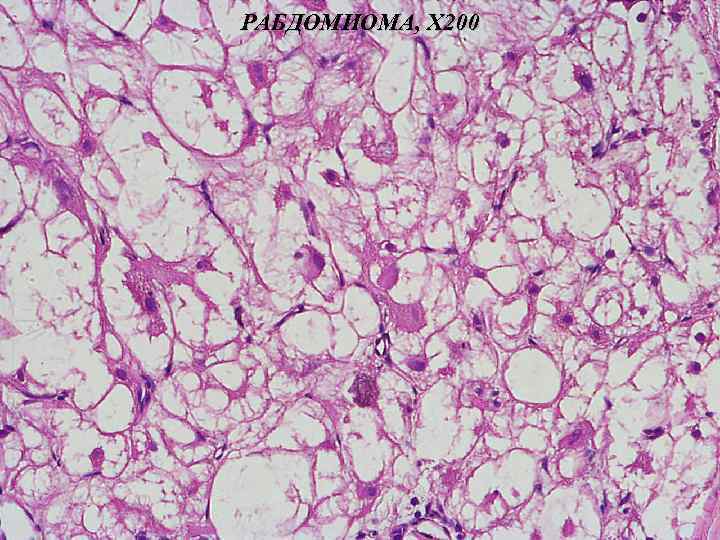

Микропрепараты: Лимфогранулематоз и Нодулярный Склероз